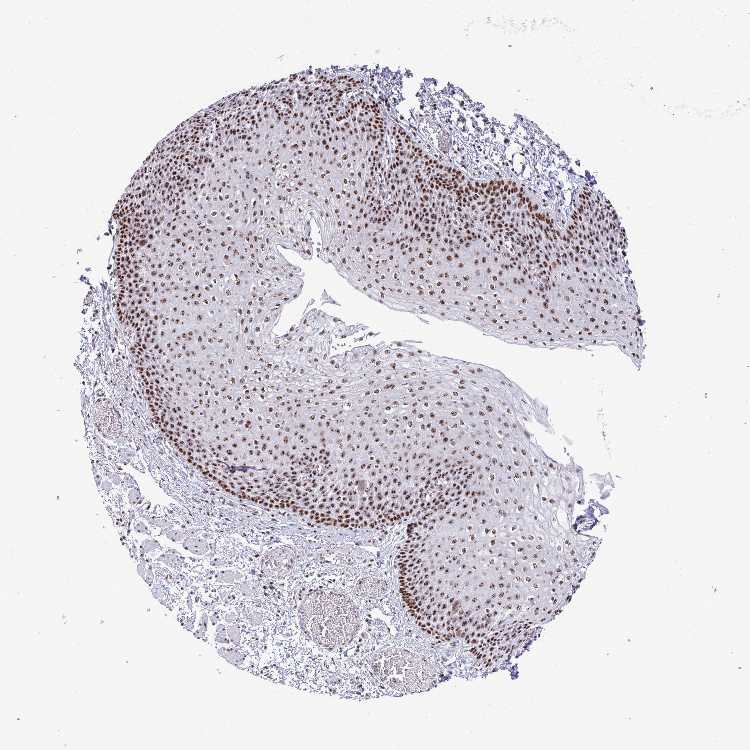

ESOPHAGUS - Antibody stainingi

Antibody staining in the annotated cell types in the current human tissue is reported as not detected, low, medium, or high, based on conventional immunohistochemistry profiling in selected tissues. This score is based on the combination of the staining intensity and fraction of stained cells.

Each image is clickable and will lead to virtual microscopy that enables deeper exploration of all samples and also displays staining intensity scores, fraction scores and subcellular localization as well as patient and tissue information for each sample.

Antibody HPA060760

Squamous epithelial cells High